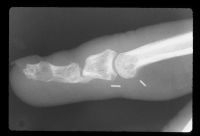

| Late films show only palmar cortical bridging and a lucency in the distal phalanx which was visible in the original films, consistent with an epidermal inclusion cyst. The patient admitted to many open and crushing fingertip injuries over the years in his line of work. |